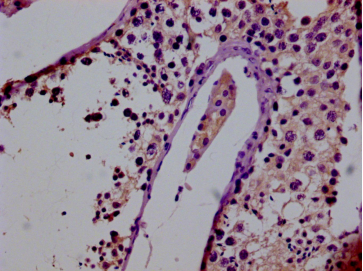

• IHC image of CSB-PA722571LA01HU diluted at 1:50 and staining in paraffin-embedded human testis tissue performed on a Leica BondTM system. After dewaxing and hydration, antigen retrieval was mediated by high pressure in a citrate buffer (pH 6.0). Section was blocked with 10% normal goat serum 30min at RT. Then primary antibody (1% BSA) was incubated at 4°C overnight. The primary is detected by a biotinylated secondary antibody and visualized using an HRP conjugated SP system.